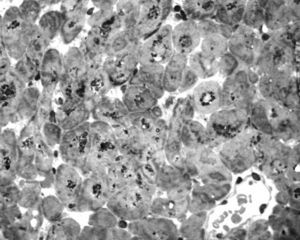

To further investigate the relationship between this morphological finding and Fabry cardiomyopathy in a female with Fabry disease and no other evidence of cardiac involvement, a transjugular endomyocardial biopsy was obtained. Histopathological examination of myocardial fragments from the right ventricle showed marked deposition of glycosphingolipids in cardiomyocytes, sparing the endothelial cells (Figures 5 and 6). Based on this finding, the patient was proposed for enzyme replacement therapy.